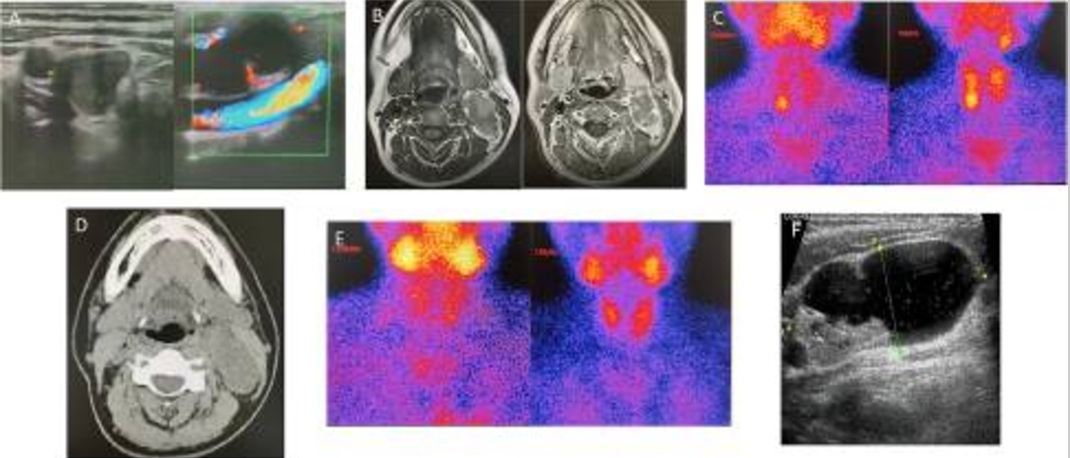

一名44岁的女性因恶心、呕吐和四肢无力10个月余就诊。体格检查提示高血压,收缩压超过200mmHg。实验室检查提示,患者血清总钙为4.84 mmol/L(参考范围:2.1-2.6 mmol/L),甲状旁腺激素水平为1396.5 pg/mL(参考范围为12.00-88.00 pg/mL)。根据Marcella D Walker和Shonni J Silverberg的诊断治疗指南,她被诊断为pHPT。术前颈部超声检查(US)报告中,考虑靠近右甲状腺叶下侧的肿物为右甲状旁腺腺瘤,左颈动脉鞘中的囊实性肿物被怀疑是神经鞘瘤,这与磁共振成像(MRI)一致(图1A,B)。99mTc-Sestamibi闪烁扫描(MIBI)(图1C)显示右下甲状旁腺肿物摄取;因此,患者被怀疑患有右下甲状旁腺腺瘤。MIBI在左颈动脉鞘内的囊实性肿物中呈阴性。

图1 超声显示靠近右甲状腺叶下侧的肿物和位于左颈动脉鞘内的囊实性肿物(a);MRI显示左颈动脉鞘内有一个囊实性肿物,大小约为48 mmX25 mmX39 mm,边界清晰。实部T1WI信号略低,T2WI信号略高,囊部T1WI和T2WI信号均匀高(B);MIBI显示在右下甲状旁腺肿物中摄取(C);CT显示左颈动脉鞘中有46 mmx23 mm的肿物(D);术后MIBI检查为阴性(E);左侧颈部肿物的US图像(F)

图2 第一次术后病理

手术后,患者的症状持续存在,PTH水平(范围:276.30–615.2 pg/mL)和血清钙(范围:2.43–3.24 mmol/L)没有显著下降(图3)。随后,计算机断层扫描(CT)报告左颈动脉鞘中肿物,而MIBI结果仍然为阴性(图1D,E)。正电子发射断层扫描(PET)也没有显示左颈部肿物的代谢增加,考虑为神经源性肿瘤,符合之前怀疑的神经鞘瘤。在此期间,患者接受了唑来膦酸治疗。然而在治疗期间,血清钙仍然高于正常范围。

随后患者转院治疗,血压略高(151/101mmHg),颈部可见一4厘米手术疤痕,愈合良好。左胸锁乳突肌后可见肿物,表面光滑,边界清晰,活动正常,无压痛。实验室检查显示高钙血症和甲状旁腺激素水平升高。此外,患者还出现低钾血症(2.8 mmol/L,参考范围:3.5–5.3 mmol/L),尿钙增加(7.9 mmol/24 h,参考范围为2.5–7.5 mmol/24小时),尿磷减少(13.5 mmol/24 h,参考范围16.1–42 mmol/24)。双X射线吸收仪(DXA)检测骨质疏松程度(T评分:-2.5或以下),腰椎(L1–L4)、股骨颈和髋关节的骨密度(BMD)值(单位为g/cm2)分别为0.731、0.559和0.694。T评分分别为-2.9、-2.6和-2.0。颈部超声检查还提示,左颈动脉鞘中的肿物可能是神经鞘瘤(图1F)。为了明确病变位置,进行了SVS,在左侧甲状腺中静脉和上静脉发现了最高的快速PTH峰值(图4)。

这一结果高度提示,左颈动脉鞘的囊实性肿物中存在产生甲状旁腺激素的组织,怀疑甲状旁腺异位。患者随后接受了第二次手术,切除左颈动脉鞘中5.5cm × 2.5cm × 2cm的肿物。异位甲状旁腺腺瘤的最终病理诊断得到证实(图5)。第二次手术后的第一天,患者的血清钙和甲状旁腺激素水平已恢复正常,恶心、呕吐和虚弱症状也在术后缓解。

图5 第二次术后病理